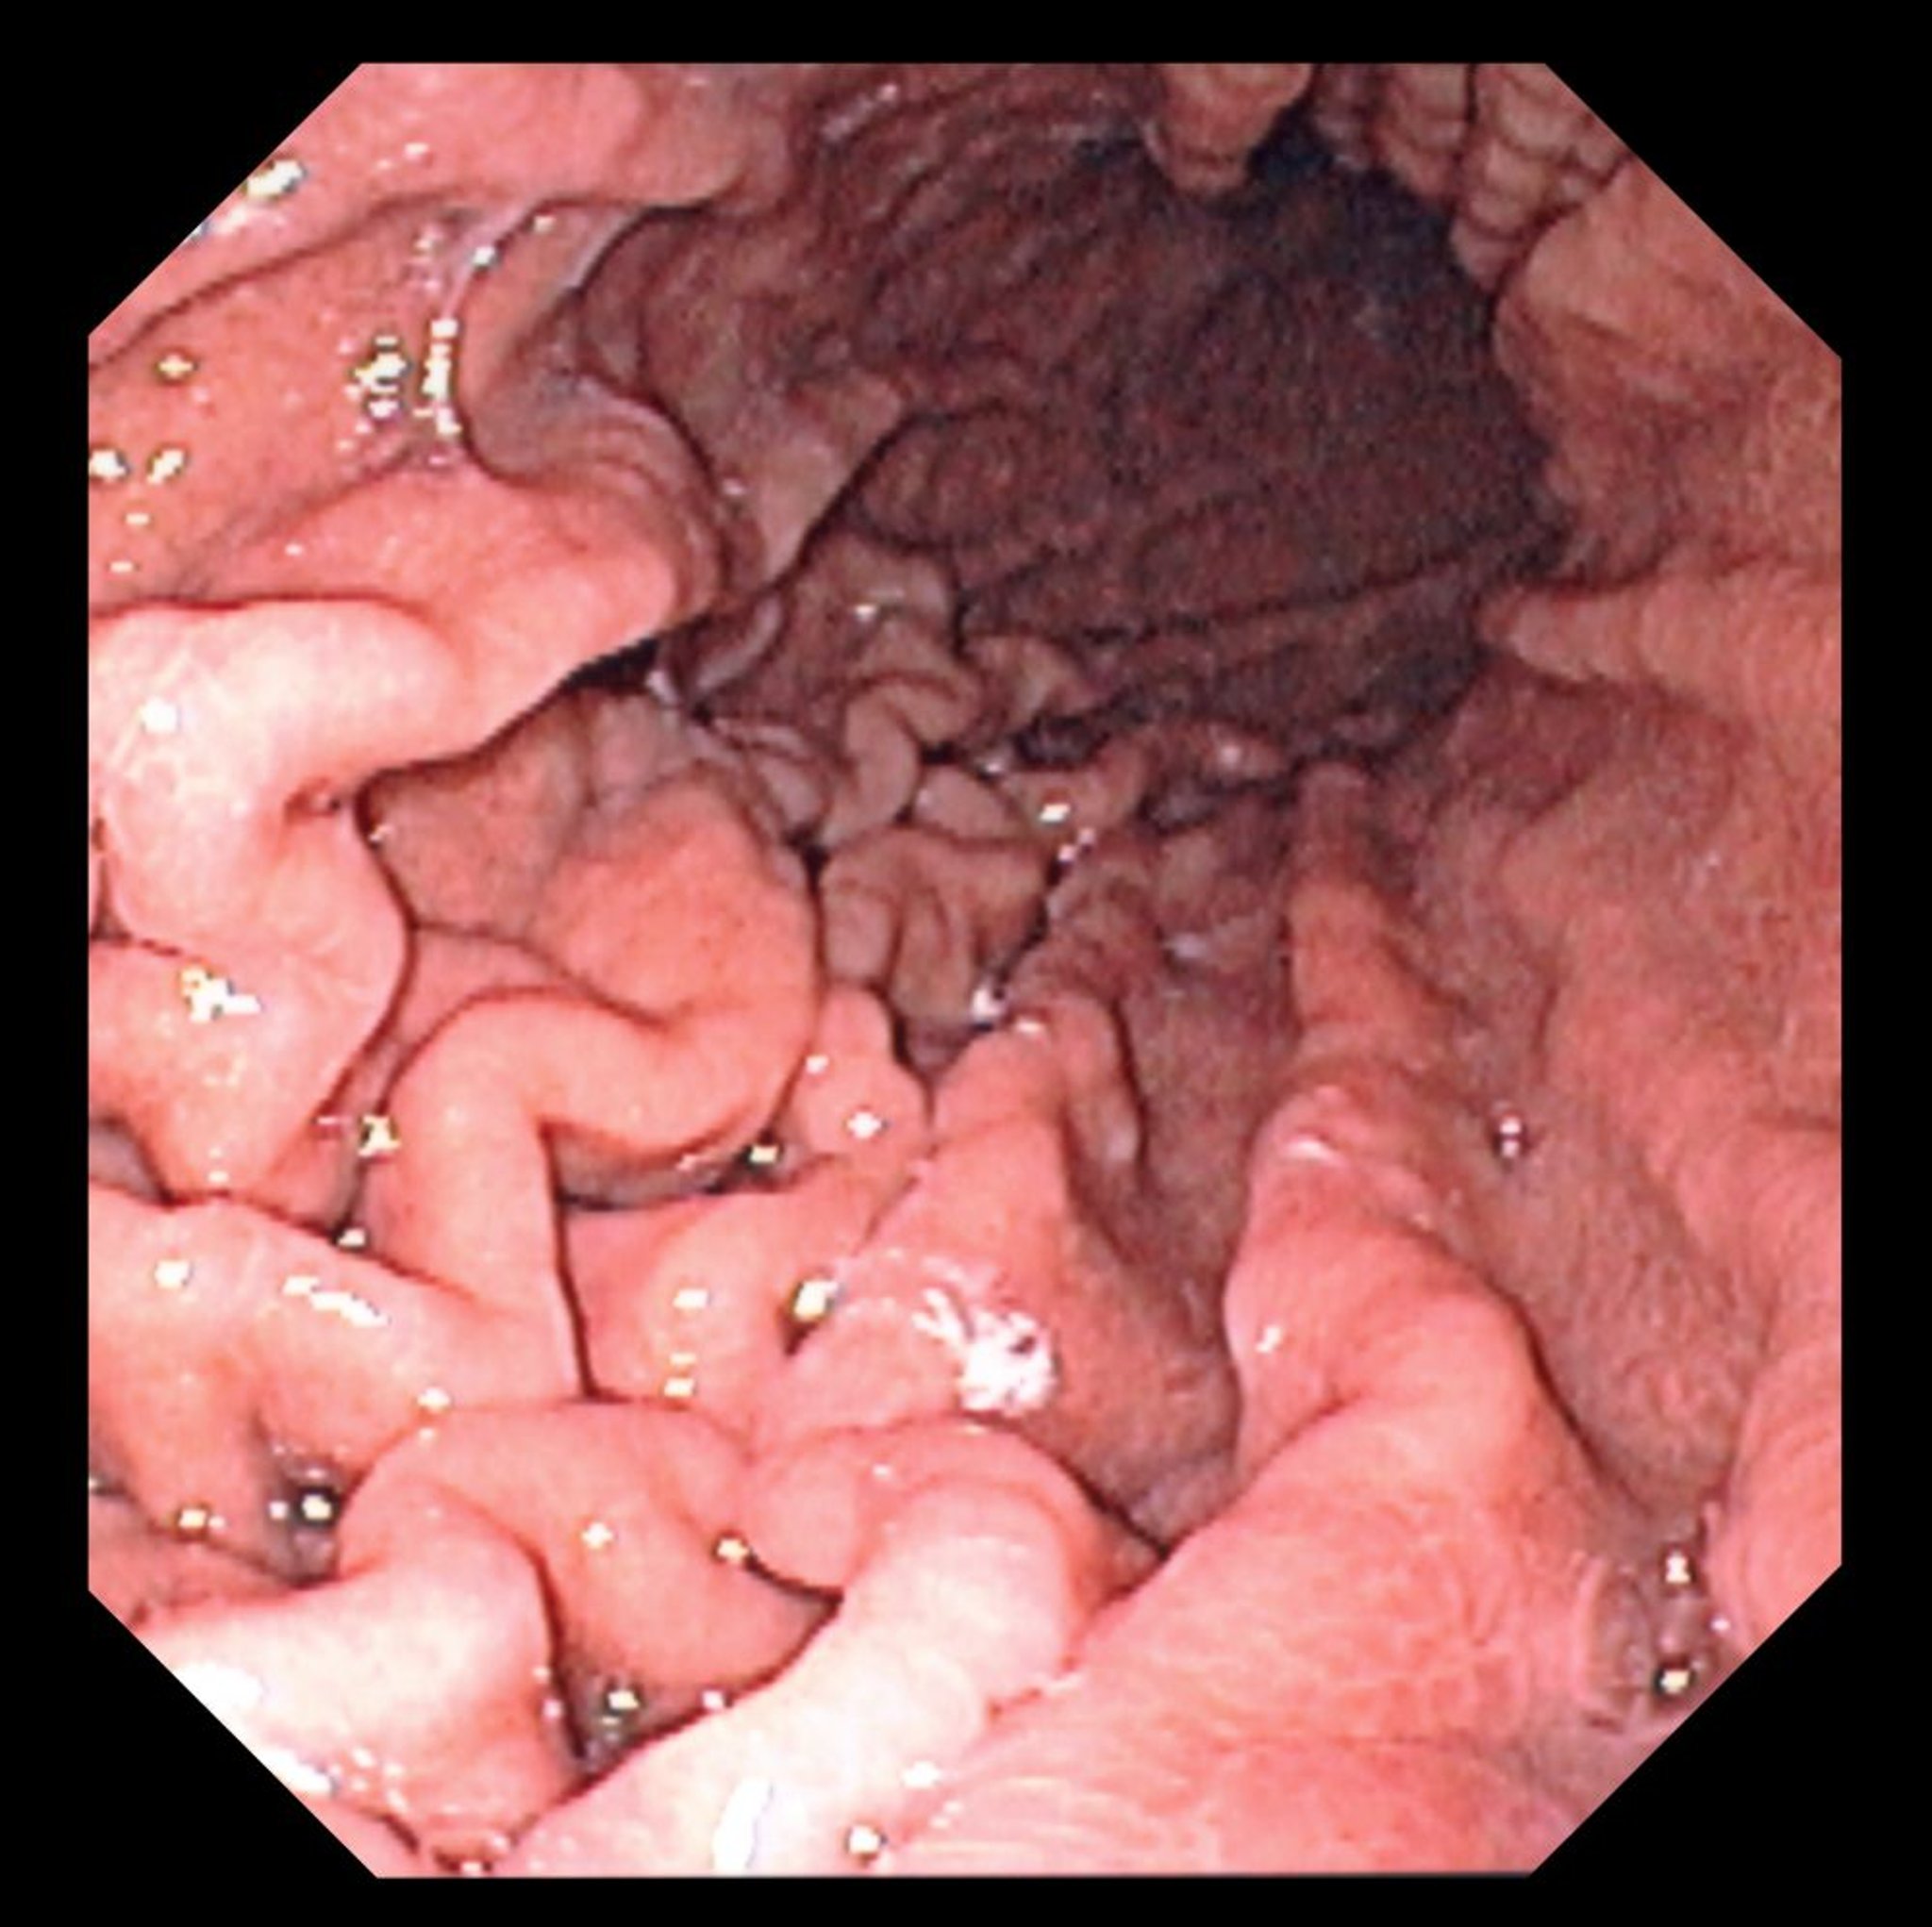

Cette photo montre une vue endoscopique d'un fundus de l'estomac normal avec des plis gastriques caractéristiques.

DAVID M. MARTIN, MD/SCIENCE PHOTO LIBRARY